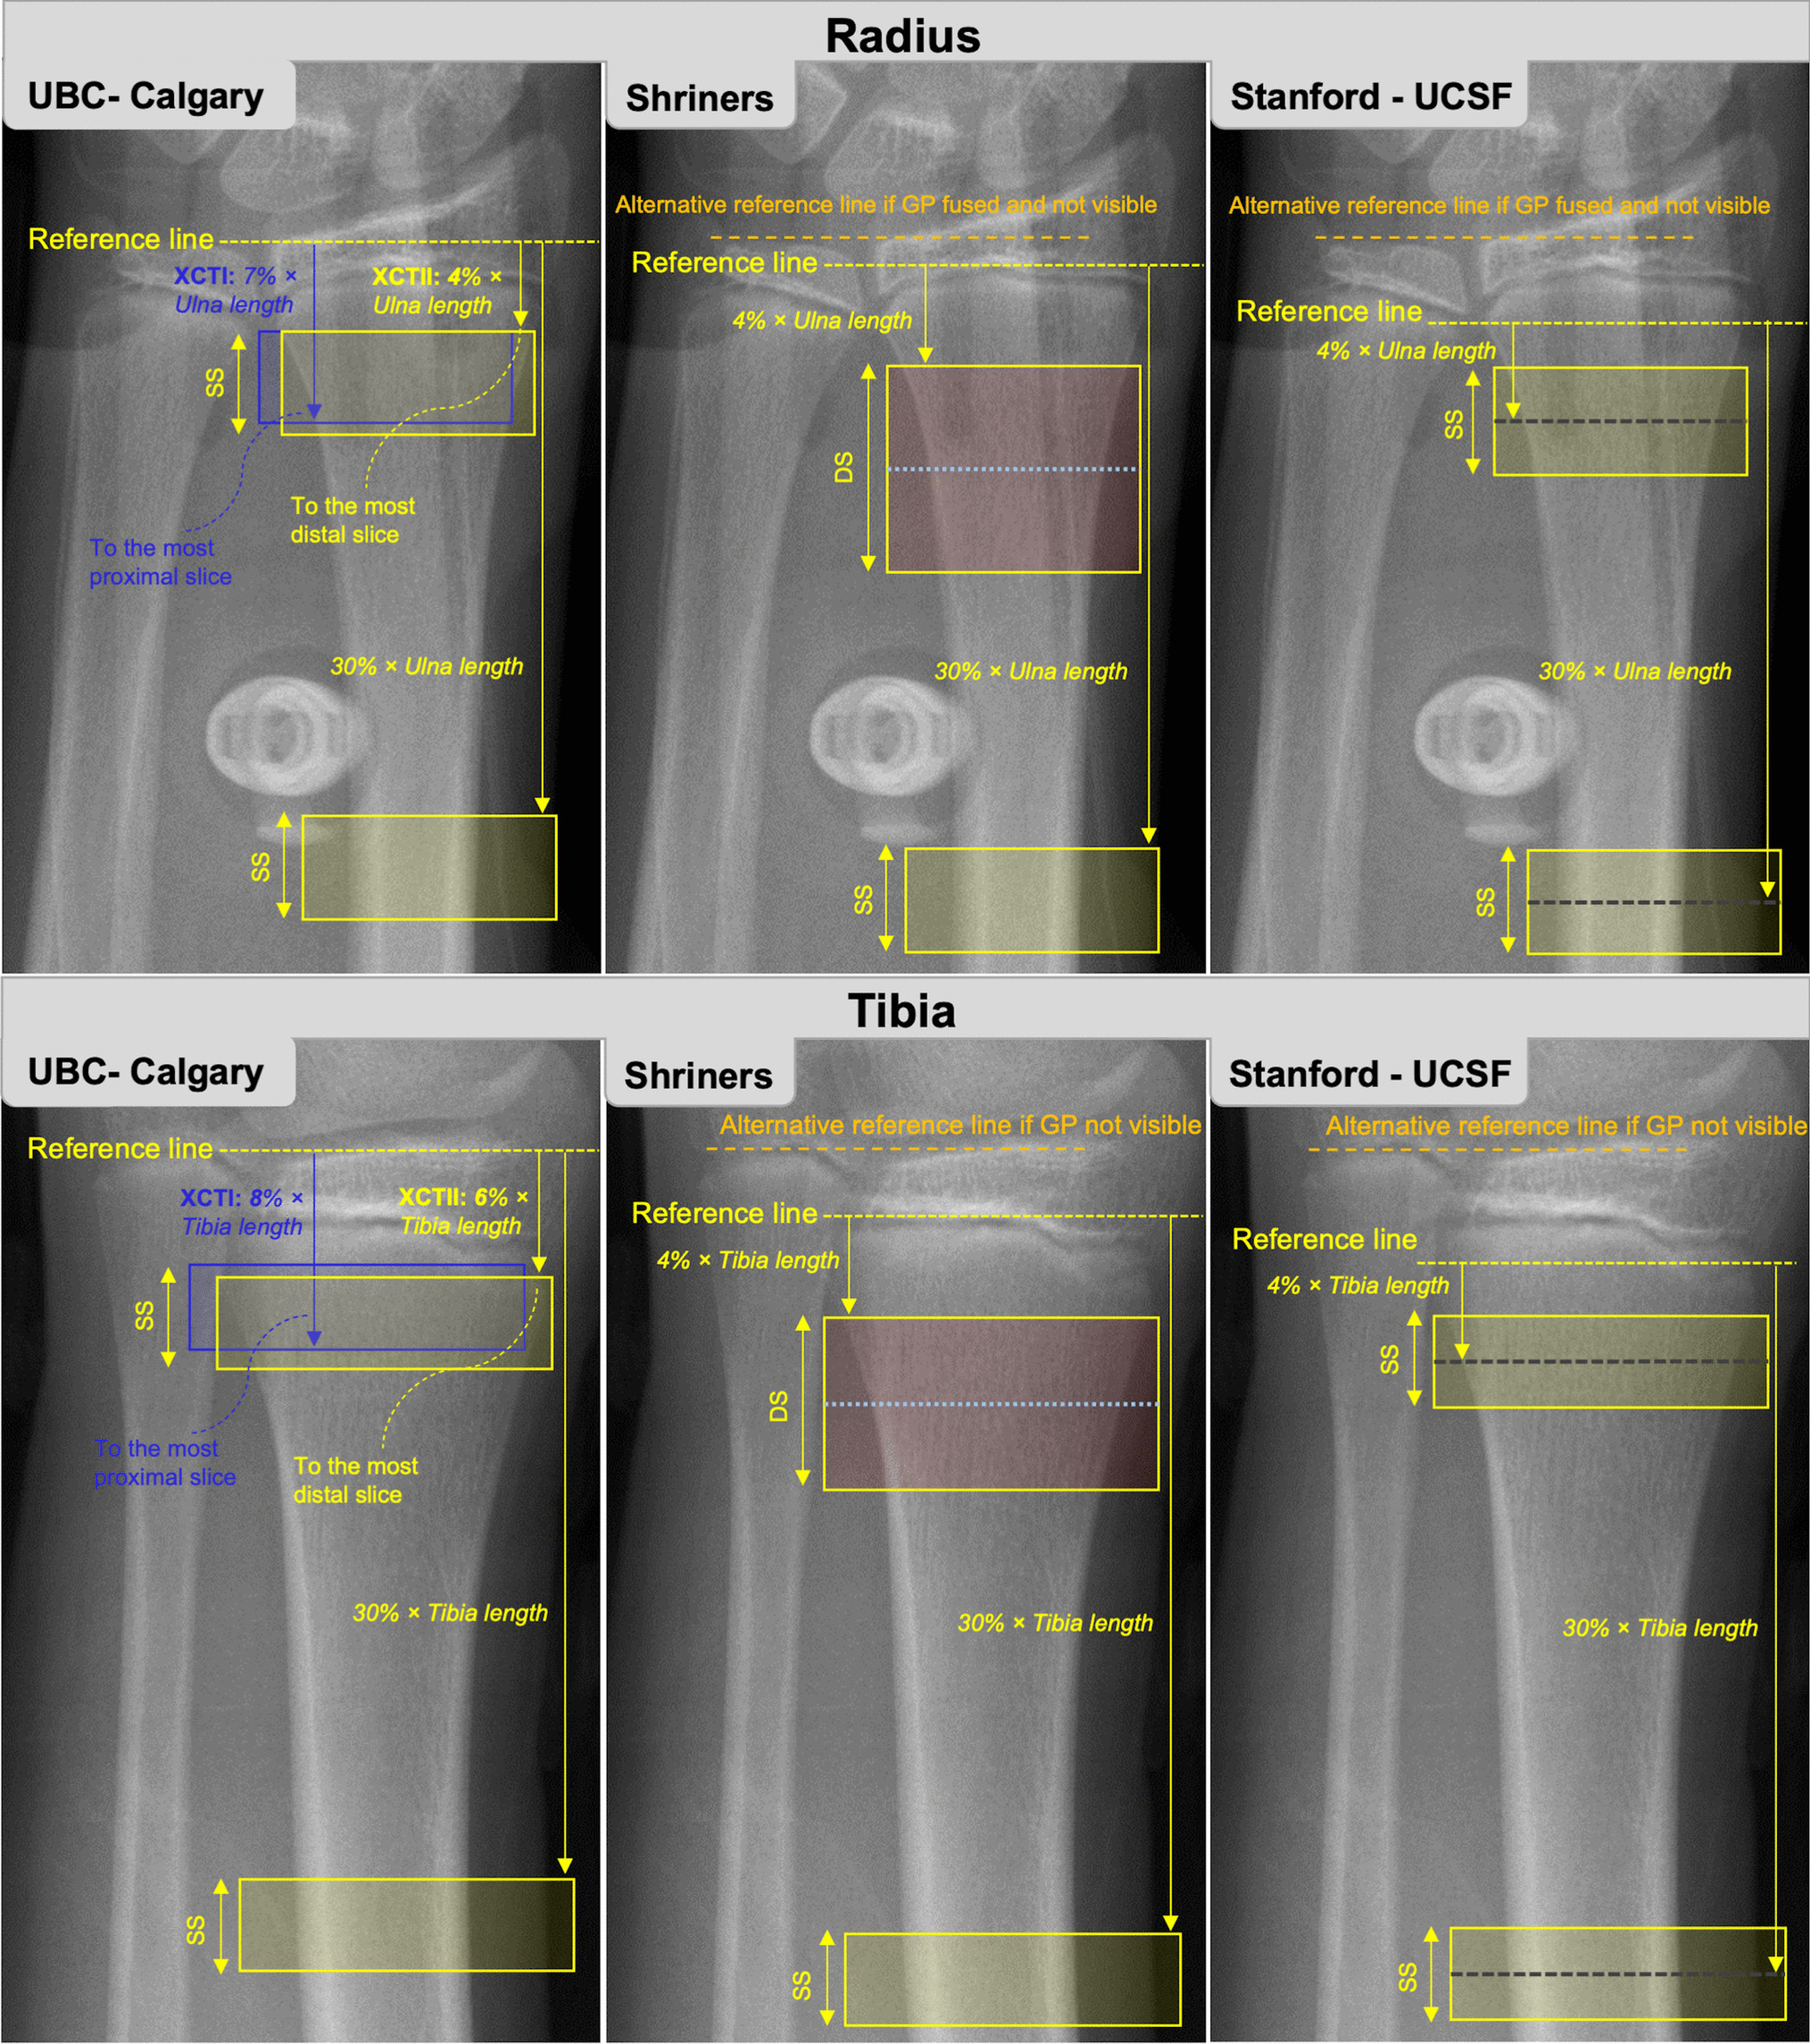

Fig. 3

Reference line placement for current pediatric HR-pQCT protocols at the radius (top row) and tibia (bottom row). UBC, University of British Columbia; XCTI, first-generation HR-pQCT; XCTII, second-generation HR-pQCT; GP, growth plate; SS, single stack; DS, double stack

University of British Columbia Protocol

The University of British Columbia (UBC) developed a protocol using a relative ROI for children and adolescents using XCTI. In this protocol, the reference line location is placed at the distal tibia plateau or medial proximal margin of the distal radius (Fig. 3). Scans proceed proximally toward the 8% site of the distal tibia (% of total tibia length) or 7% site of the distal radius (% of total ulnar length), such that the 8% and 7% sites are the most proximal scan slice. The 8% and 7% ROI include both cortical and trabecular bones and exclude the growth plate in most children [28, 30]. This protocol was used throughout the mixed-longitudinal UBC Healthy Bones Study [1, 3, 3642], for developing normative data for XCTI in children and adolescents [9], and by other research groups [4346].

To avoid encroaching on the growth plate with an additional 1.0-mm scan region for XCTII, the original UBC protocol has been adapted for XCTII by adding the additional 1.0-mm scan region to the proximal end of the scan. Further, there was some confusion around the location of the ROI in the original XCTI protocol (e.g., the last slice of the scan was the 8% or 7% site as opposed to the first slice); thus, the protocol for XCTII has been adjusted to begin at the 6% site of the distal tibia and 4% site of distal radius and scan proximally from there. With this revised approach, the most proximal slice of the scans ends near the 8% and 7% sites of the distal tibia and radius, respectively, as in the XCTI protocol (Fig. 3). Although microarchitectural parameters differ between XCTI and XCTII, total BMD should remain comparable between the two scanners and can be related to existing XCTI normative data (spanning age 9 through 21 years) [9].

Shriners Protocol

The Shriners Hospital for Children-Canada (McGill University) developed another variation of relative ROI positioning for children using XCTII. In this protocol, the reference line location depends on the status of the growth plate. If the growth plate is open, the reference line is placed at the most distal margin of the distal growth plate for both the radius and tibia (Fig. 3). When the growth plate fuses with no visible remnant, it can be difficult to identify the most distal margin; thus, the reference line is placed at the medial proximal margin of the radial articular surface and at the tibial plateau, which are locations recommended for reference line placement in adults (Fig. 3) [8•, 31]. The scanned region begins at 4% of ulna or tibia length from the reference line and proceeds with a double stack (two sequential scans; 20.4 mm stack length; see the “Double Stack Scanning” section). Note that a single stack can be used instead of a double stack, since we encourage reporting each stack separately. Similar protocols for the radius and tibia make the protocol more straightforward for radiology technicians to perform. Also, extensive reference data from pQCT are available for the 4% region in children [19, 3335, 47]. This protocol excludes inadvertently scanning the growth plate in all participants. One disadvantage of the protocol is that if the growth plate fuses and becomes indistinguishable during the study period, one must switch landmarks for reference line placement (from the pediatric to adult protocol) for a participant’s subsequent imaging. However, at the radius, the distance between the most distal margin of the growth plate and the medial proximal margin of the radial endplate is small; thus, switching between landmarks when the growth plate fuses results in minimal change to the volume of interest scanned. In practice, the need for switching between landmarks is rarely required since even in case of growth-plate fusion, some remnants will be visible such that using the pediatric landmarks is feasible.

Stanford/University of California San Francisco Protocol

The Stanford SAMBA Lab and University of California San Francisco (UCSF) developed another variation of relative ROI positioning for children and adolescents that uses the proximal margin of the growth plate as the reference line. The reference line is set at the most proximal edge of the growth plate, growth plate remnant, or scar (Fig. 3). The scanned region is centered at 4% of ulna or tibial length from the reference line. This location centers the scan ROI in a standard location in the metaphysis with respect to the endochondral ossification front. The proximal edge of the growth plate can be challenging to locate when the growth plate is fusing. Further, the most proximal edge may be medial, central, or lateral, so technicians must be trained to look at the entire growth plate. If the growth plate is fused and there is no visible growth plate, growth plate remnant, or scar, then the reference line would move to the endplate (adult reference line) and the standard adult relative offset protocol would be used. This occurs more often at the radius and almost never at the tibia. A reference line placement module will soon be available to help train operators locating this region.

With the longer XCTII gantry, cortical bone parameters can be assessed at diaphyseal sites. The UBC and Shriners protocols assess diaphyseal bone at 30% of ulna or tibia length relative to their respective reference lines, while the Stanford protocol centers the stack at 30% of ulna or tibia length relative to the reference line. Outcomes of interest at the 30% site include total and cortical area, cortical BMD, thickness, and porosity.